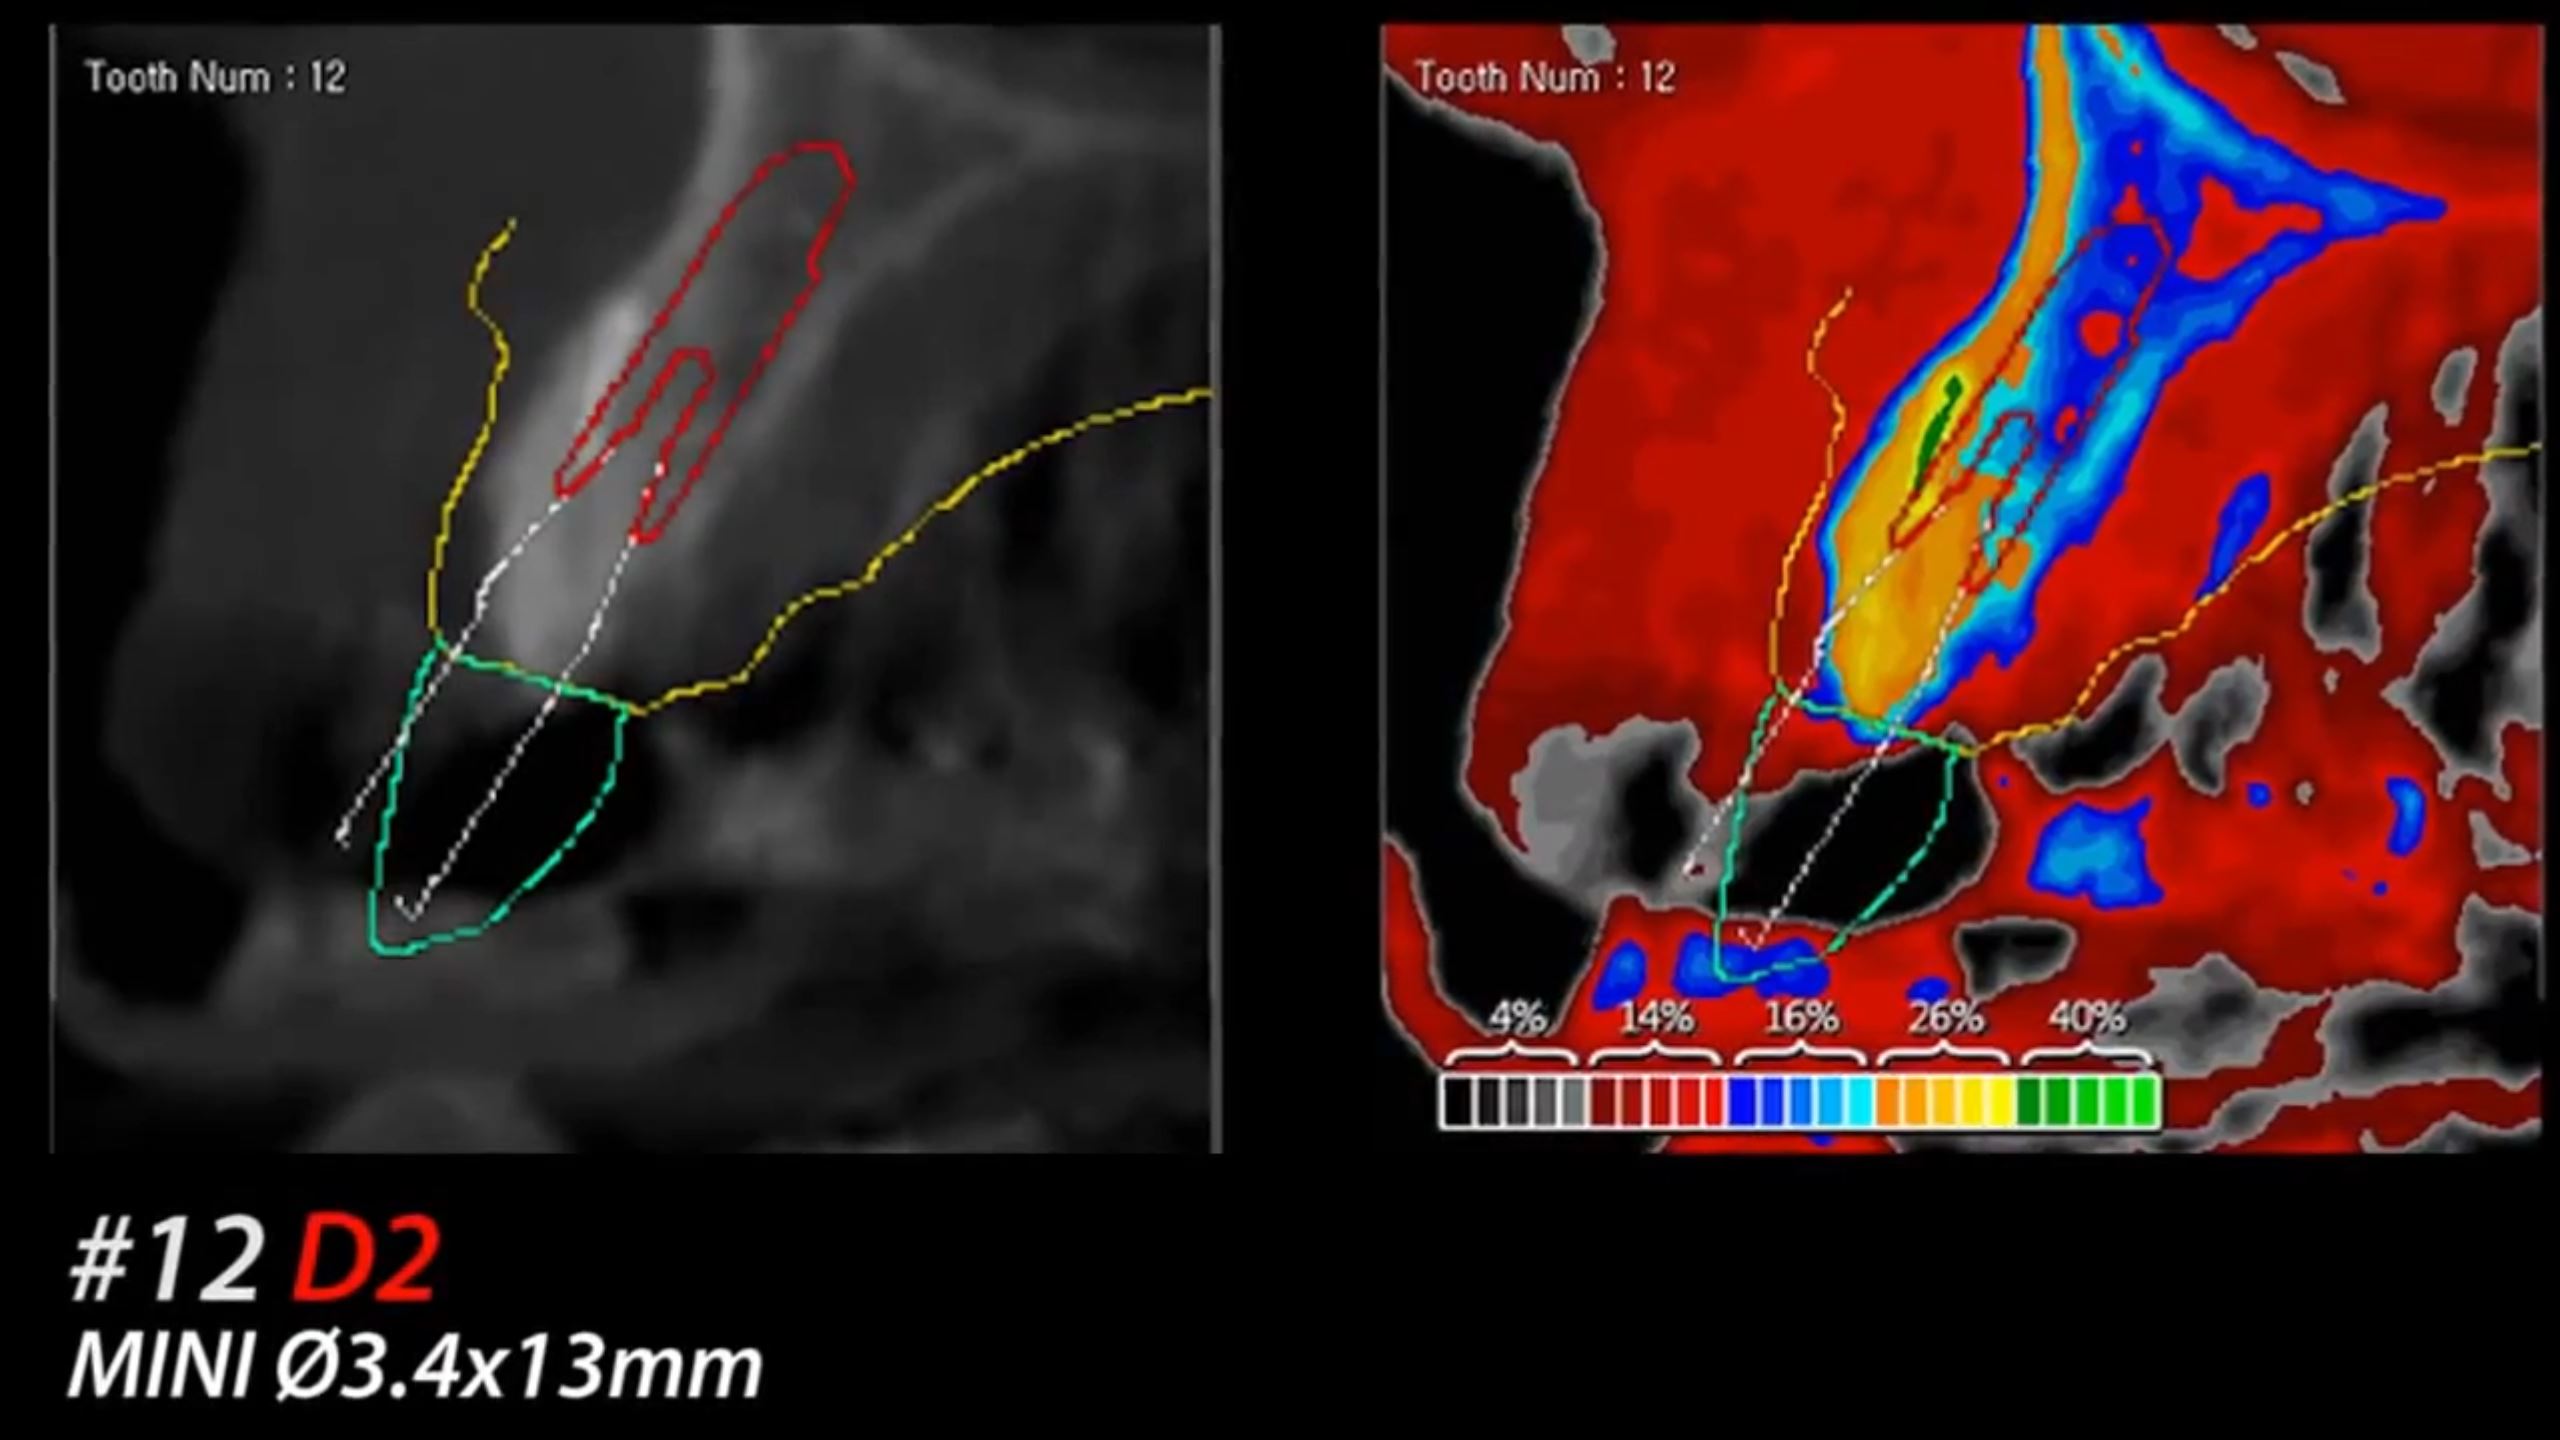

R2GATE Guide Surgery with MiNi

Dr. Kwang Bum Park,Immediate loading,Digital Guided Surgery,Maxillary Anterior,#12,Guided surgery,Immediate Placement,Flapless,MiNi,R2GATE Guide,MEG-TORQ,MEGA ISQ,Video